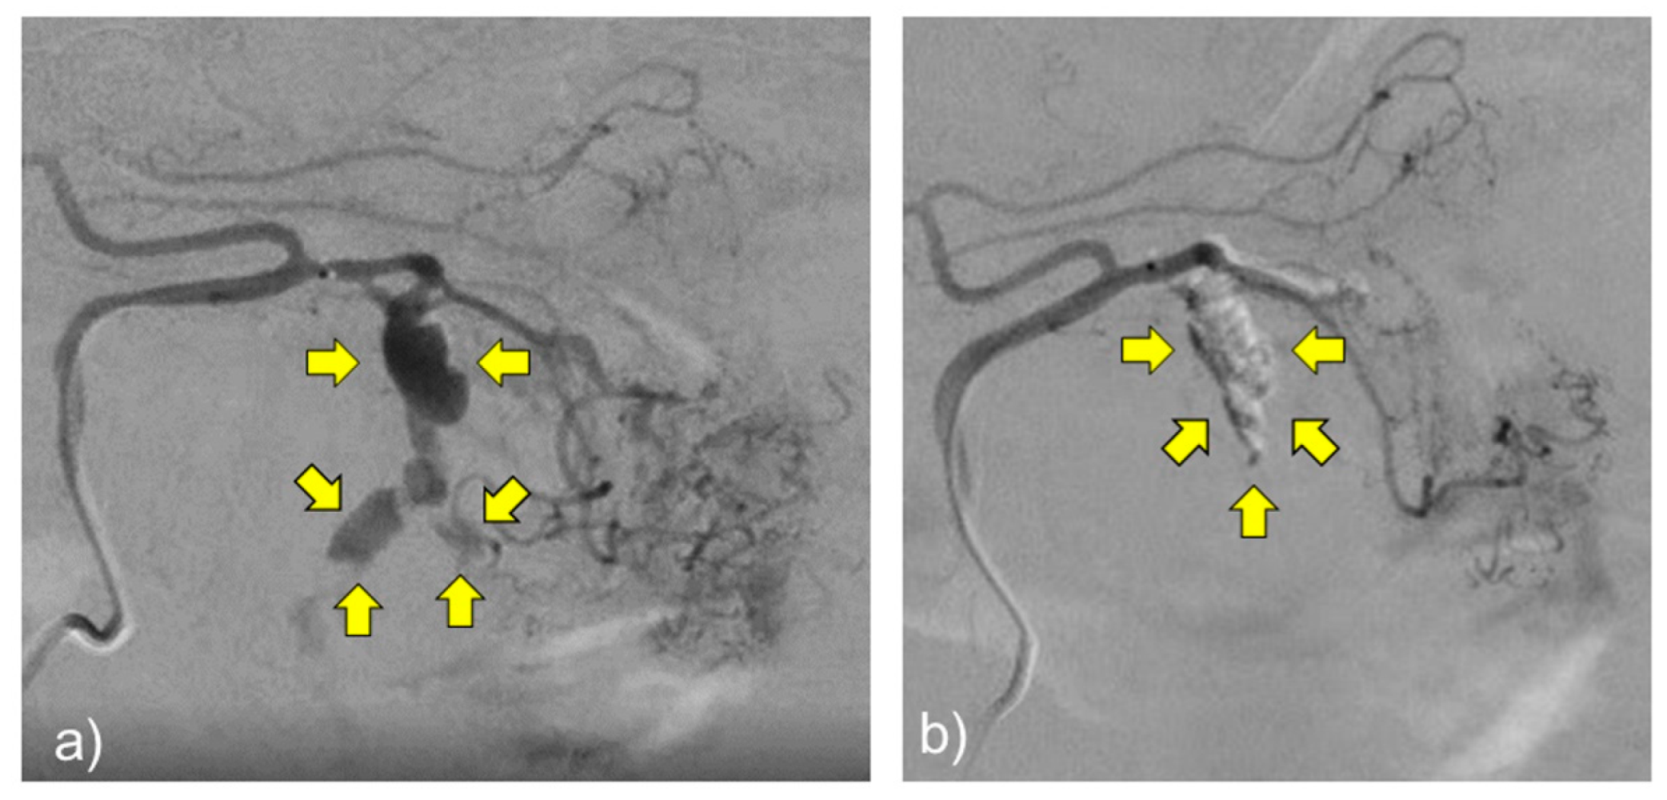

2. Case Presentation